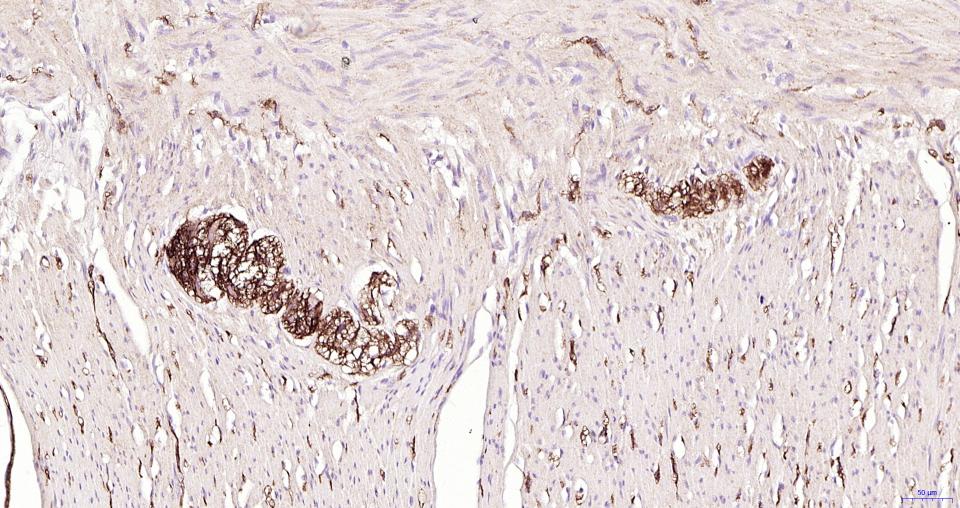

细胞粘附蛋白(Call Adhesion Protein) 神经元标志物 NCAM-1为神经细胞粘附分子,主要分布于神经组织,神经—肌肉接头,神经—内分泌腺和某些内分泌腺以及大多数神经外胚层来源的细胞、组织和肿瘤中。 NCAM 1主要用于视网膜母细胞瘤、髓母细胞瘤、星形细胞瘤、神经母细胞瘤等肿瘤方面的研究。CD56(神经细胞黏附分子,NCAM)表达于大部分神经外胚层来源的细胞系、组织和肿瘤如视网膜母细胞瘤、成神经管细胞瘤、星形细胞瘤以及成神经细胞瘤。它也表达于一些中胚层来源的肿瘤如横纹肌肉瘤。NK细胞以及NK细胞淋巴瘤为阳性。CD56被认为是NK细胞肿瘤的重要标志物。该抗体识别分子量为180,145和125kDa亚型。